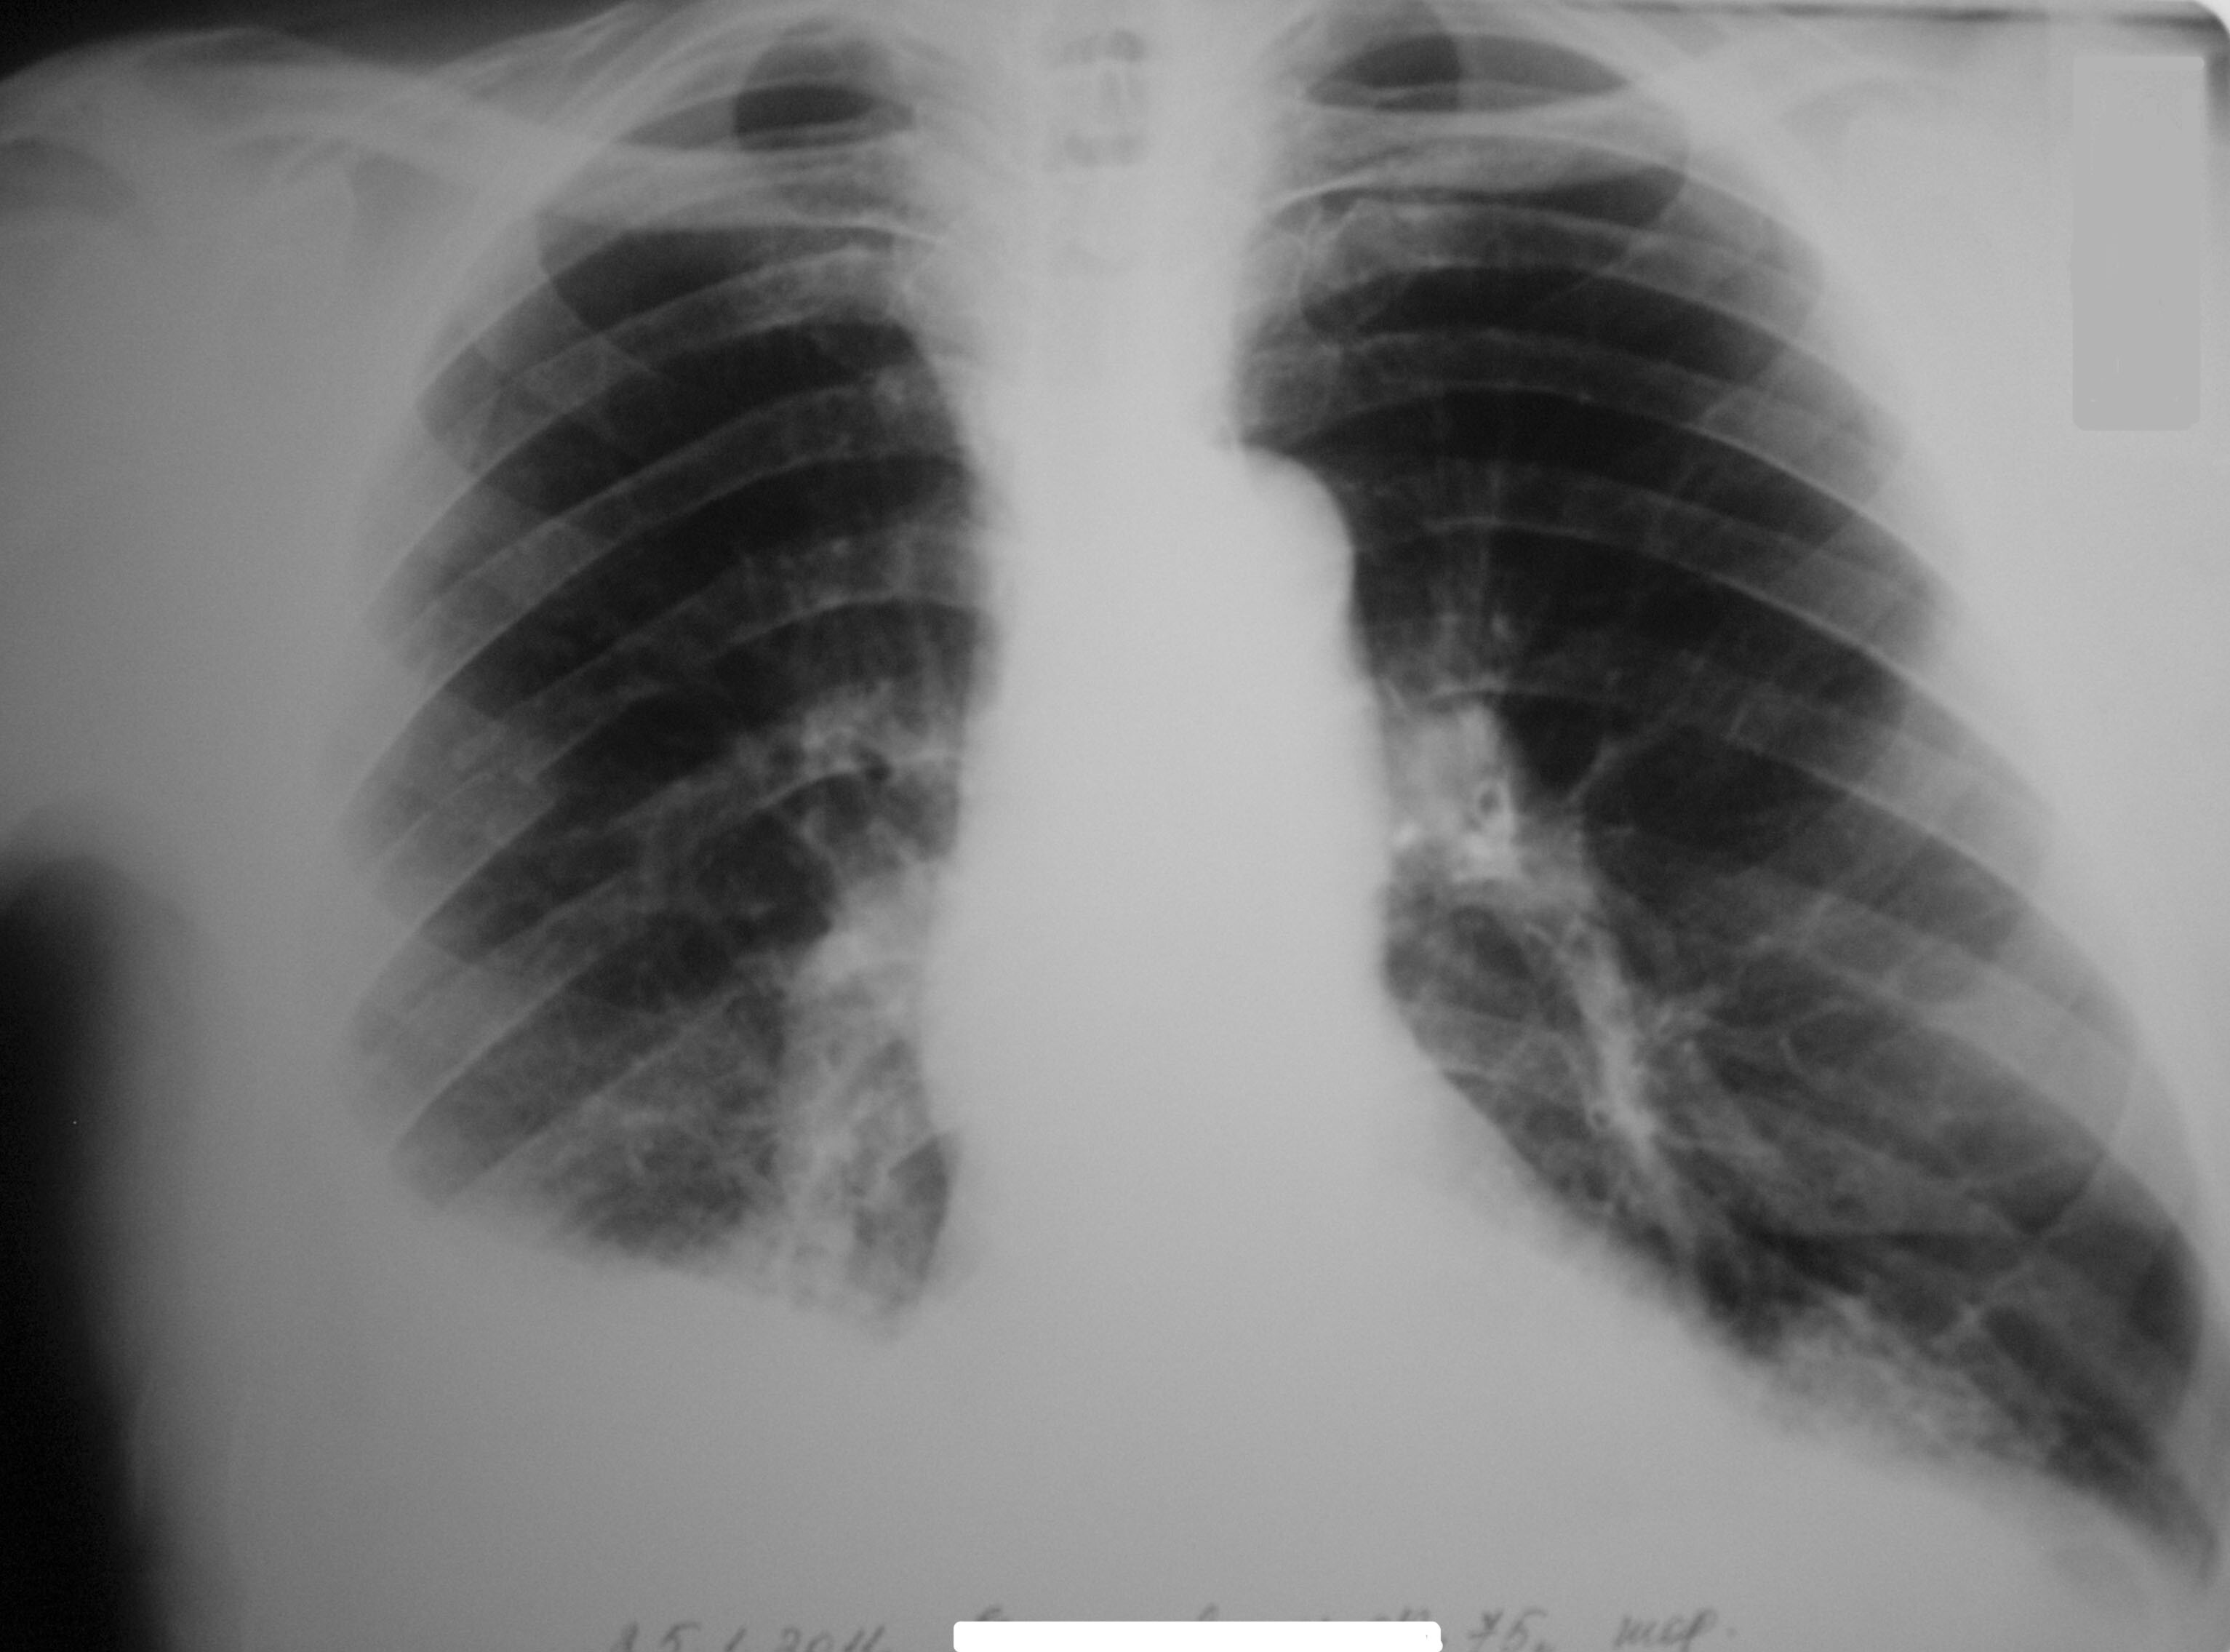

Курение кальяна повышает риск развития рака легких, полости рта, гортани и мочевого пузыря. Кроме этого, вредная привычка угрожает здоровью сердечно-сосудистой системы. Курение кальяна несколькими людьми грозит туберкулезом и другими инфекциями.

Фото: commons.wikimedia.org, Клеткин Максим Евгеньевич, Creative Commons CC0 1.0 Universal Public Domain Dedication.